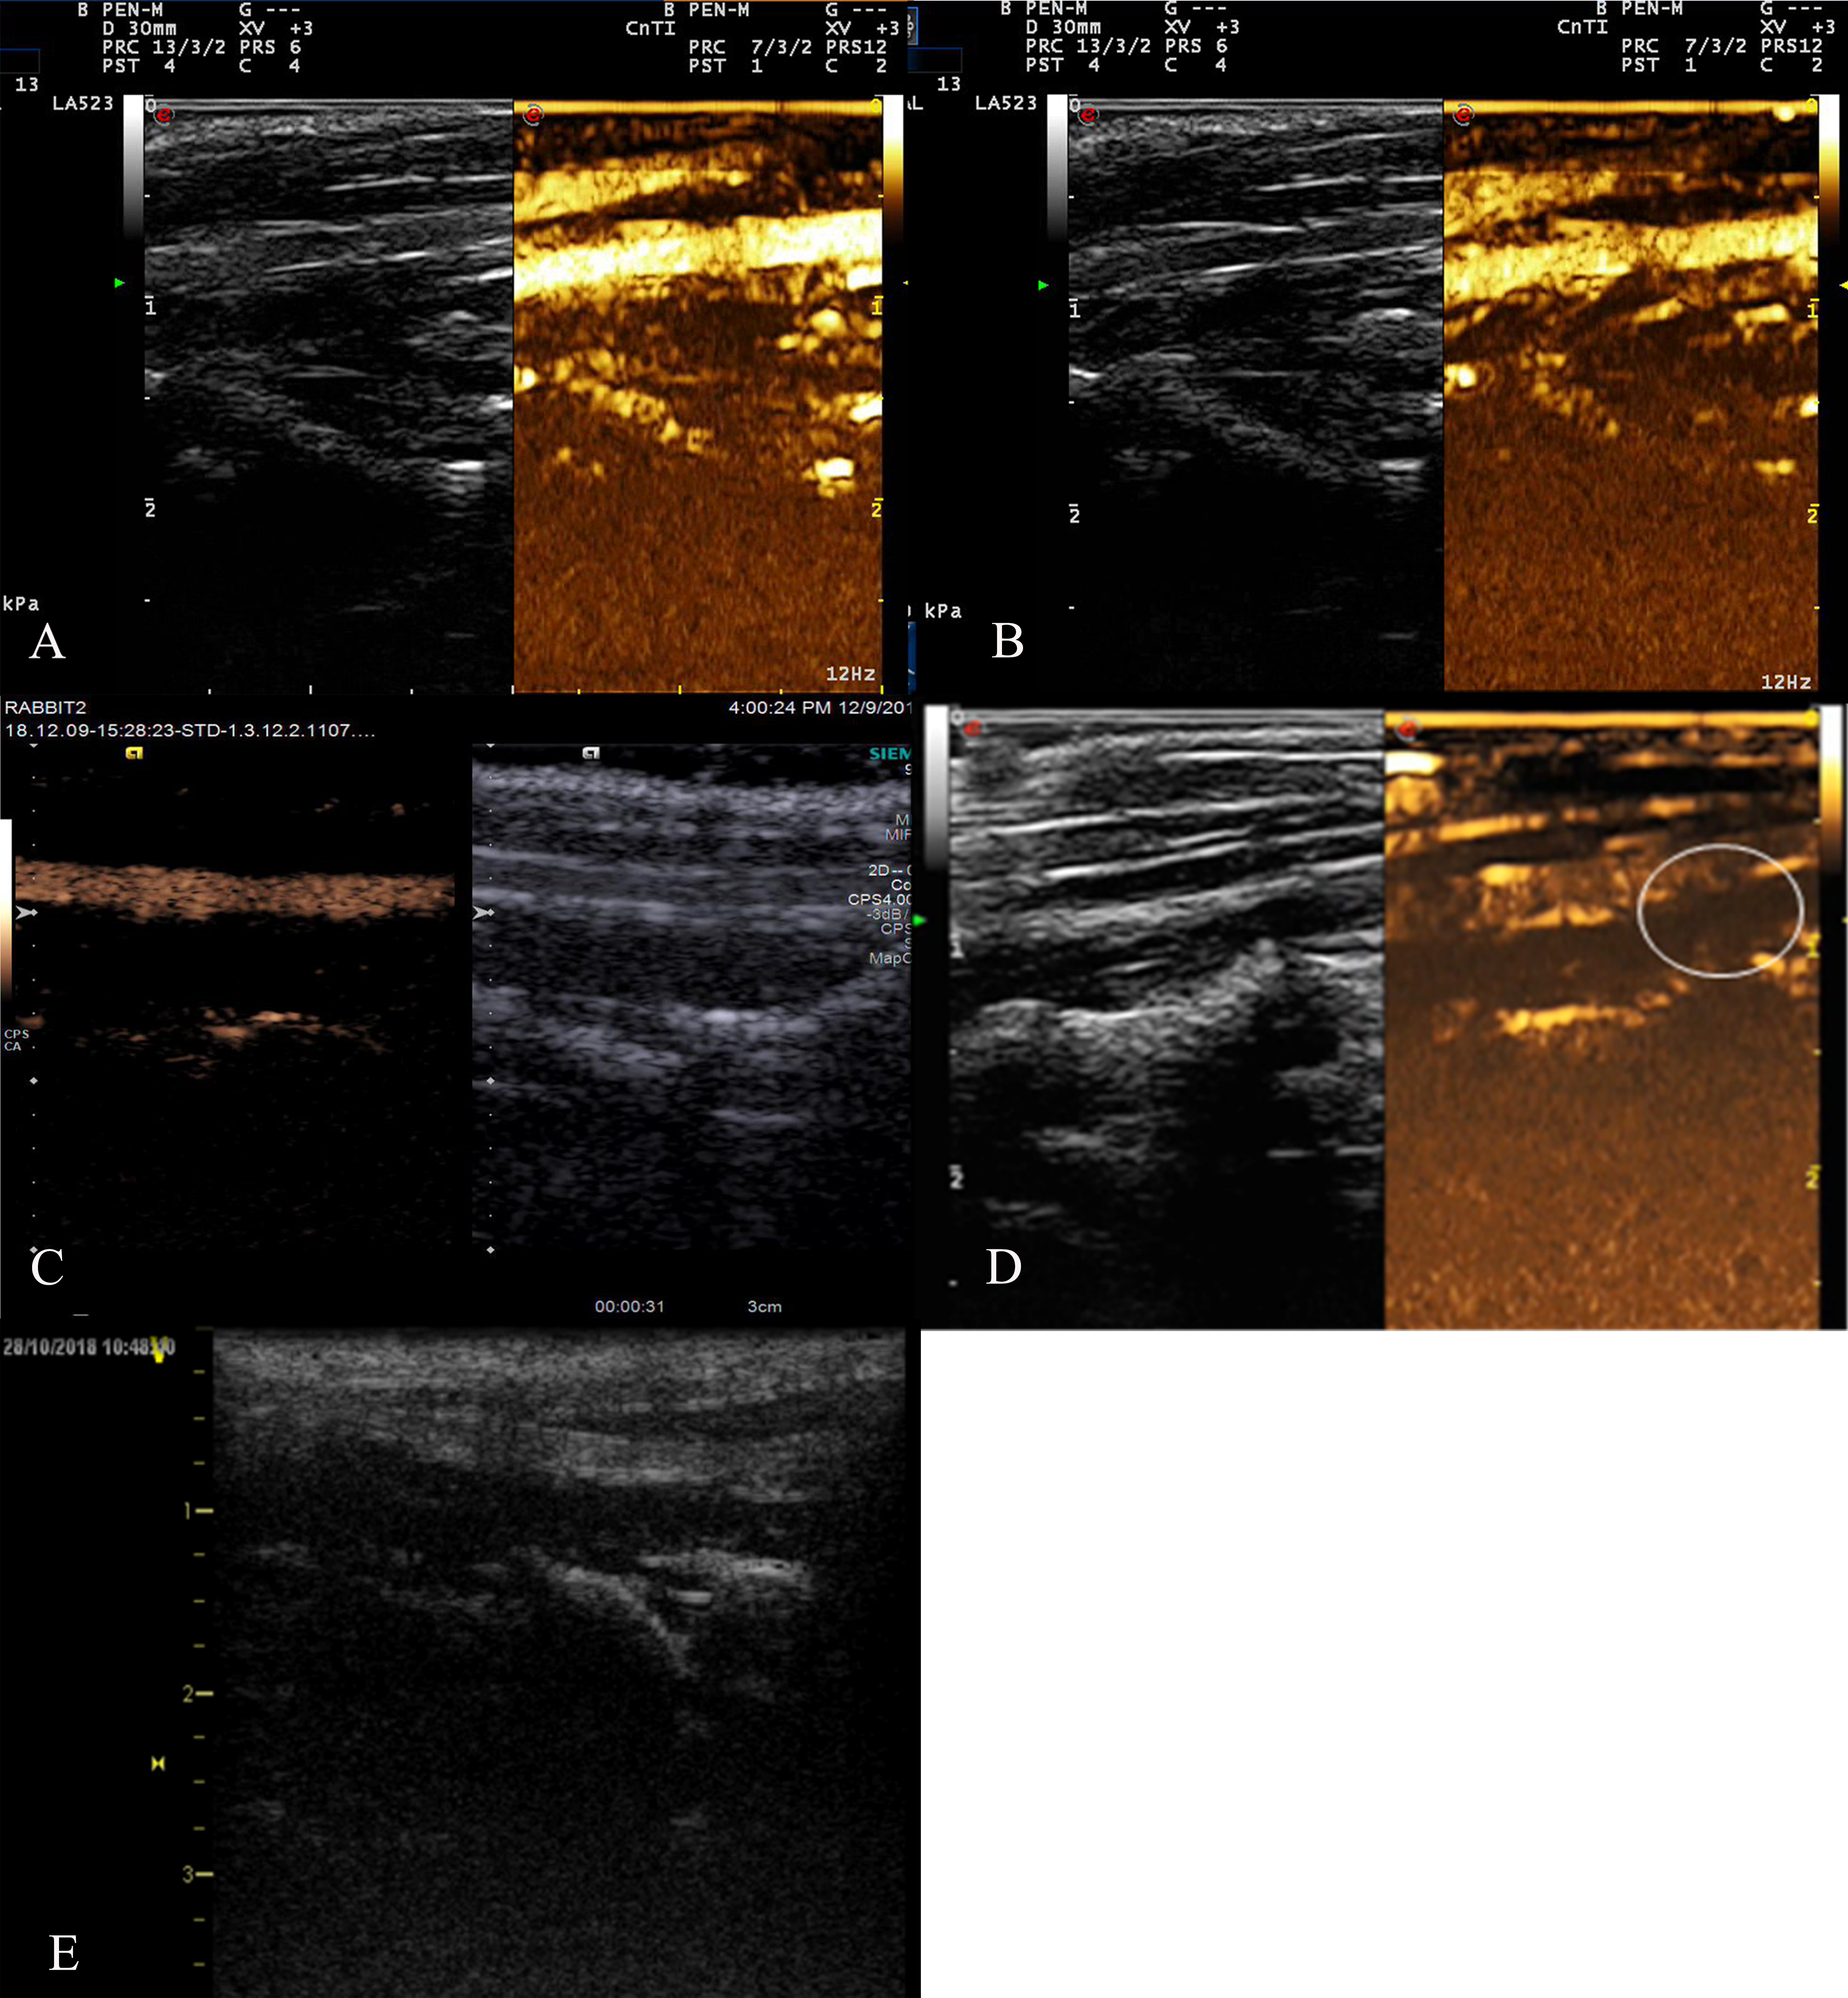

After the injection of the ultrasound contrast agent, contrast agent signal was observed in the carotid lumen at 3 seconds after injection in the four groups except for the control group (Fig. 6). The arrival time inside the plaque was later than that of the the carotid lumen, and strengthening began at the plaque base and gradually progressed to the more internal portions or short linear strengthening, which was predominantly level II or level III. After the enhancement lasted for several minutes, the enhancement effect at the plaque gradually weakened, and the contrast agent gradually cleared.

Fig. 6.Rabbit carotid artery contrast-enhanced ultrasound. (A) Image showing the anti-VCAM-1 nanometer contrast agent group with short linear enhancement in the plaque. (B) Image showing the nanoscale contrast agent group with dot enhancement in the plaques. (C) Anti-VCAM-1 sonovi group. (D) SonoVue group; dot enhancement was observed in all plaques. (E) Control group; no contrast agent sonogram is observed in the lumen.